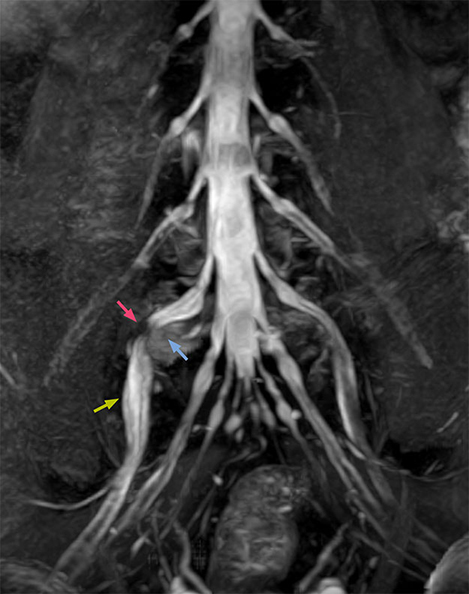

The key concept in MR neurography, Dr. Yabuki stresses, is the ability to directly visualize spinal nerves, versus inferring the presence of pathology indirectly. “Before NerveVIEW, we estimated compression of the nerve by looking for the presence or absence of fat signal on other MR images,” he says.

“For example, in sagittal images, when the presence of fat is observed in the intervertebral foramen, it suggests that there is a margin around the nerve. Similarly, the absence of fat indicates that the nerve is being compressed. So, we used to deduce nerve compression indirectly. With NerveVIEW, however, we can observe the condition of the nerves directly, regardless of the presence or absence of fat. We always prefer such direct observation of anatomy over having to make an inference about it.”

“Although symptoms of typical disc herniation and atypical hernia are very similar, the actual site of herniation is different. It is therefore important to characterize the nerve’s condition both inside and outside of the intervertebral foramina. “Conversely, if we see no abnormality in NerveVIEW, we can assume at least that there is no severe condition that requires surgery. Like this, it can help us avoid unnecessary surgery. NerveVIEW can have a tremendous impact in this way.”

“The intra-luminal signal of veins, especially around the intervertebral space, can be suppressed well with NerveVIEW. As a result, we can easily observe the detailed nerve structure around the posterior ganglion,” he says. “This is why we use 3D NerveVIEW for intraforaminal stenosis and extraforaminal stenosis/herniation (lateral disc herniation). On the other hand, if herniation is suspected to exist inside the dorsal root ganglion (DRG), balanced TFE or ProSet-FFE is applied. NerveVIEW is not suitable for evaluating the median type of herniation.” The SE-EPI DWI-based method for MR neurography works well for large FOV exams like whole-body MRI, but focal examination of nerves is often limited by the attainable spatial resolution (both inplane and slice direction) and geometric distortion. “3D NerveVIEW achieves higher in-plane resolution – close to our other routine spine sequences – and the source images can be used instead of adding a fat-suppressed T2-weighted sequence,” Tanji says.

“NerveVIEW can clearly show nerve courses and presence of nerve compression. However, when multiple abnormalities are seen, it can still be hard to determine which nerve is causing the symptoms,” says Dr. Yabuki. “In our experience so far, we see abnormal findings on NerveVIEW in about 70% of elderly patients. As the pain is usually caused by only one nerve, we thus need to find the exact corresponding nerve.” “With a nerve root block, the patient's pain is improved by infiltration of local anesthesia directly around the nerve root considered to be responsible. Knowing such nerve root block findings prior to image interpretation, helps to easily recognize abnormal findings on NerveVIEW as well. In other words, without a priori knowledge, based on symptoms and/or nerve root block findings, we must be aware of the possibility of overdiagnosis.”